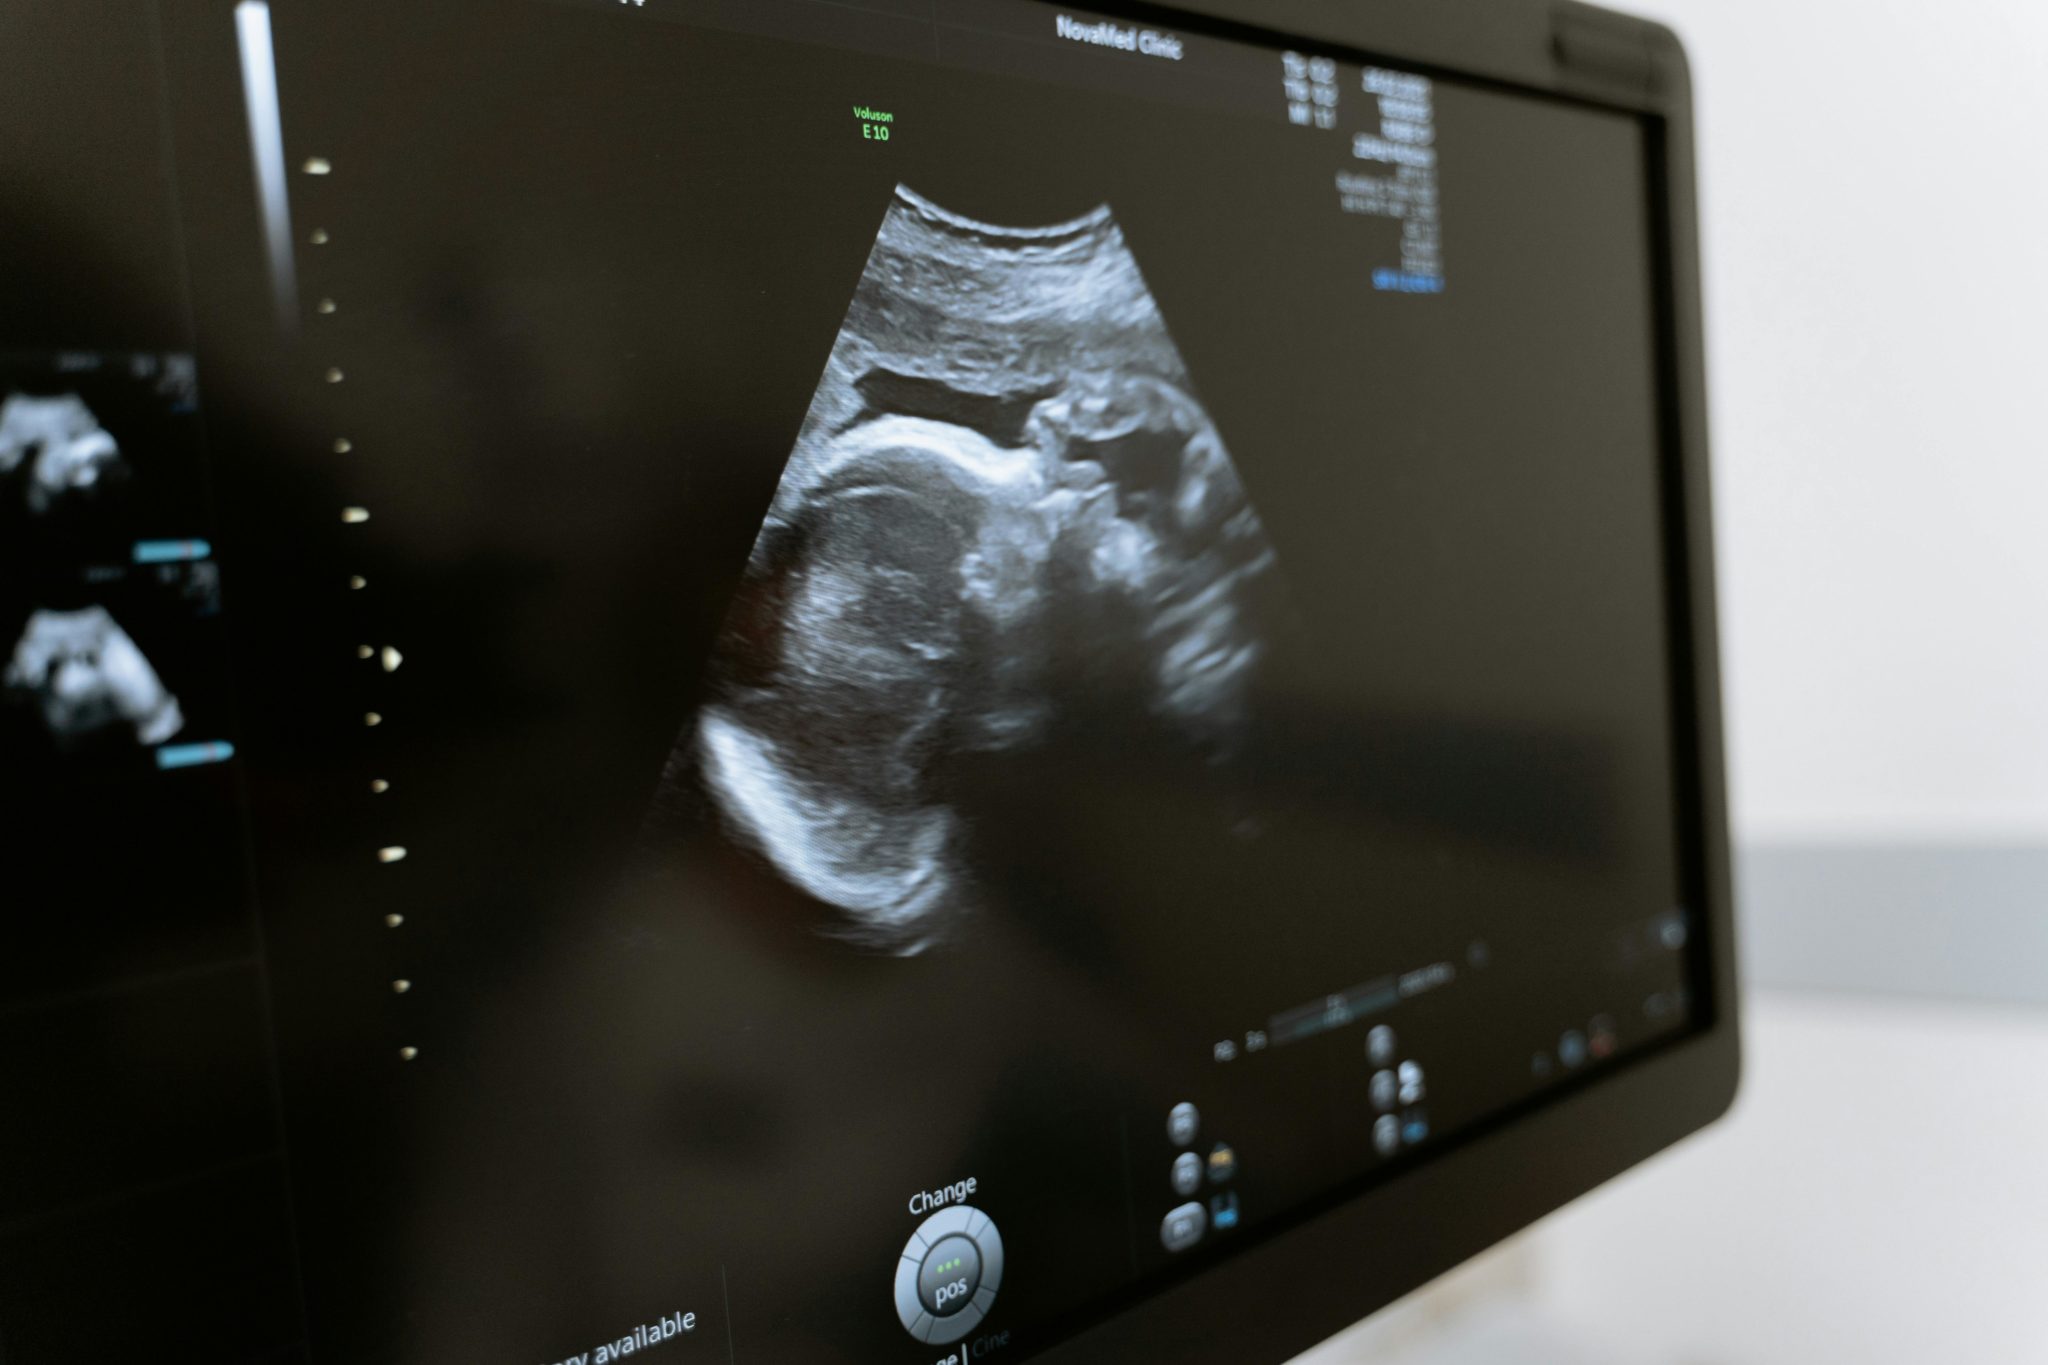

2. Une qualité d’image haute définition qui rivalise avec les systèmes fixes

Beaucoup pensent qu’un échographe portable sacrifie la qualité pour la mobilité. Cette idée est obsolète aujourd’hui. Les modèles actuels intègrent des technologies avancées comme l’imagerie harmonique tissulaire et la composition spatiale. Ces innovations garantissent une résolution élevée et des images nettes, même pour des examens complexes.

Grâce à des algorithmes de réduction du speckle et un traitement en temps réel, les détails des tissus apparaissent avec une netteté exceptionnelle. L’intégration de l’IA optimise automatiquement les paramètres d’imagerie pour une clarté maximale, même dans des conditions difficiles.

Cette précision permet des diagnostics fiables au chevet du patient, avec une pénétration jusqu’à 40 cm pour une imagerie corps entier. Pour les médecins d’urgence ou en zones isolées, cette qualité d’image permet une prise en charge rapide et efficace, sans compromis sur la précision.

Loin d’être un gadget, l’échographe portable moderne est un instrument de diagnostic robuste offrant une clarté d’image qui inspire confiance pour des décisions cliniques critiques.

- Gynécologie et obstétrique : suivi de grossesse et détection précoce du cancer de l’ovaire